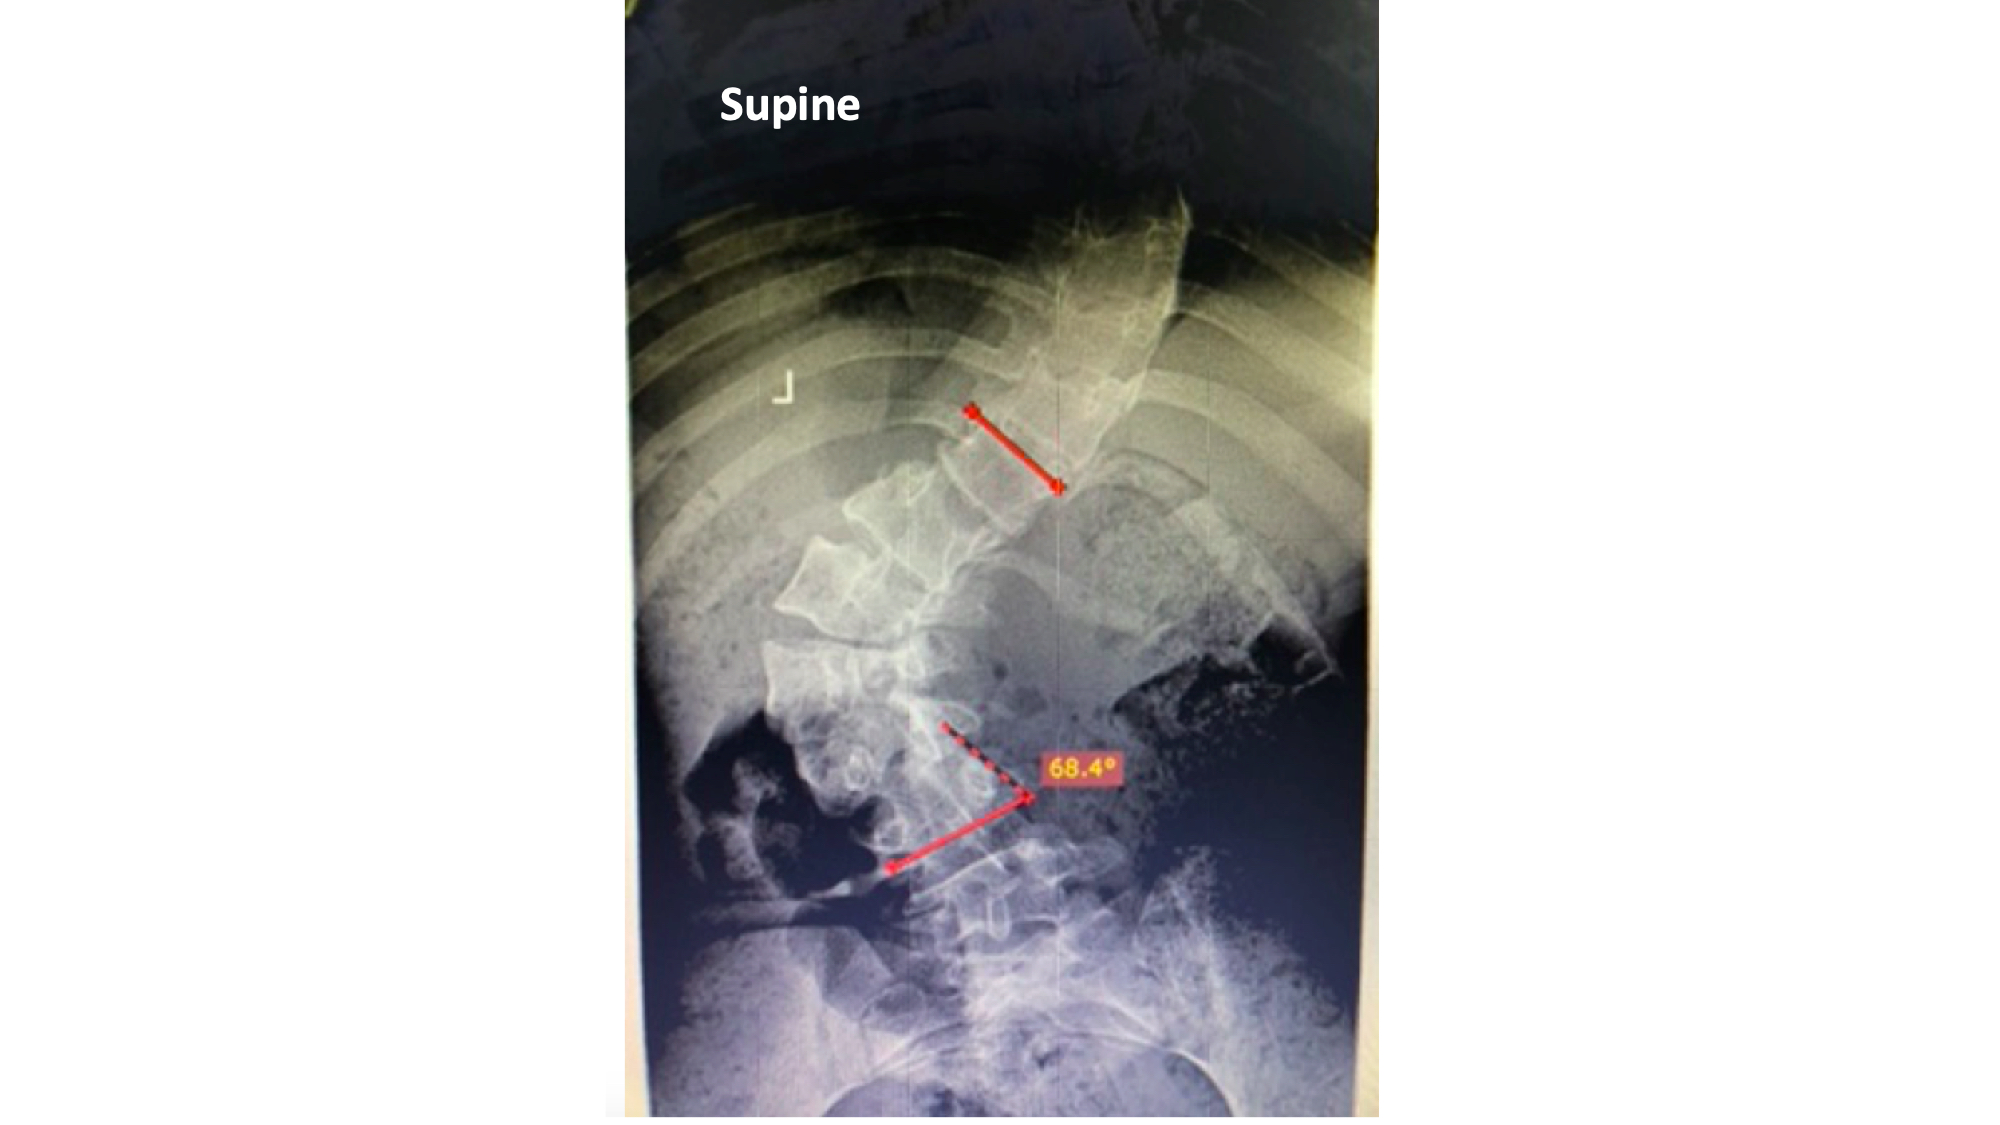

I was also able to meet the first two spine surgery fellows at AaBET. They are both neurosurgeons. The plan after next year is to alternate orthopedic with neurosurgery spine fellows. In addition to their teaching at AaBET, they are mentored by Dr Fasil Mesfin of Univeristy of Missouri, with whom they have weekly cases conferences. They were excited to show me two massive spine tumors they just operated on, one a giant, dumbbell shaped neurofibroma of the lower thoracic spine with bone involvement and preoperative paraparesis; the other a huge aneurysmal bone cyst of posterior lumbar element. Both needed pedicle screw instrumentation and big exposures. I am not a spine surgeon but the operative photos and postop xrays were very impressive.